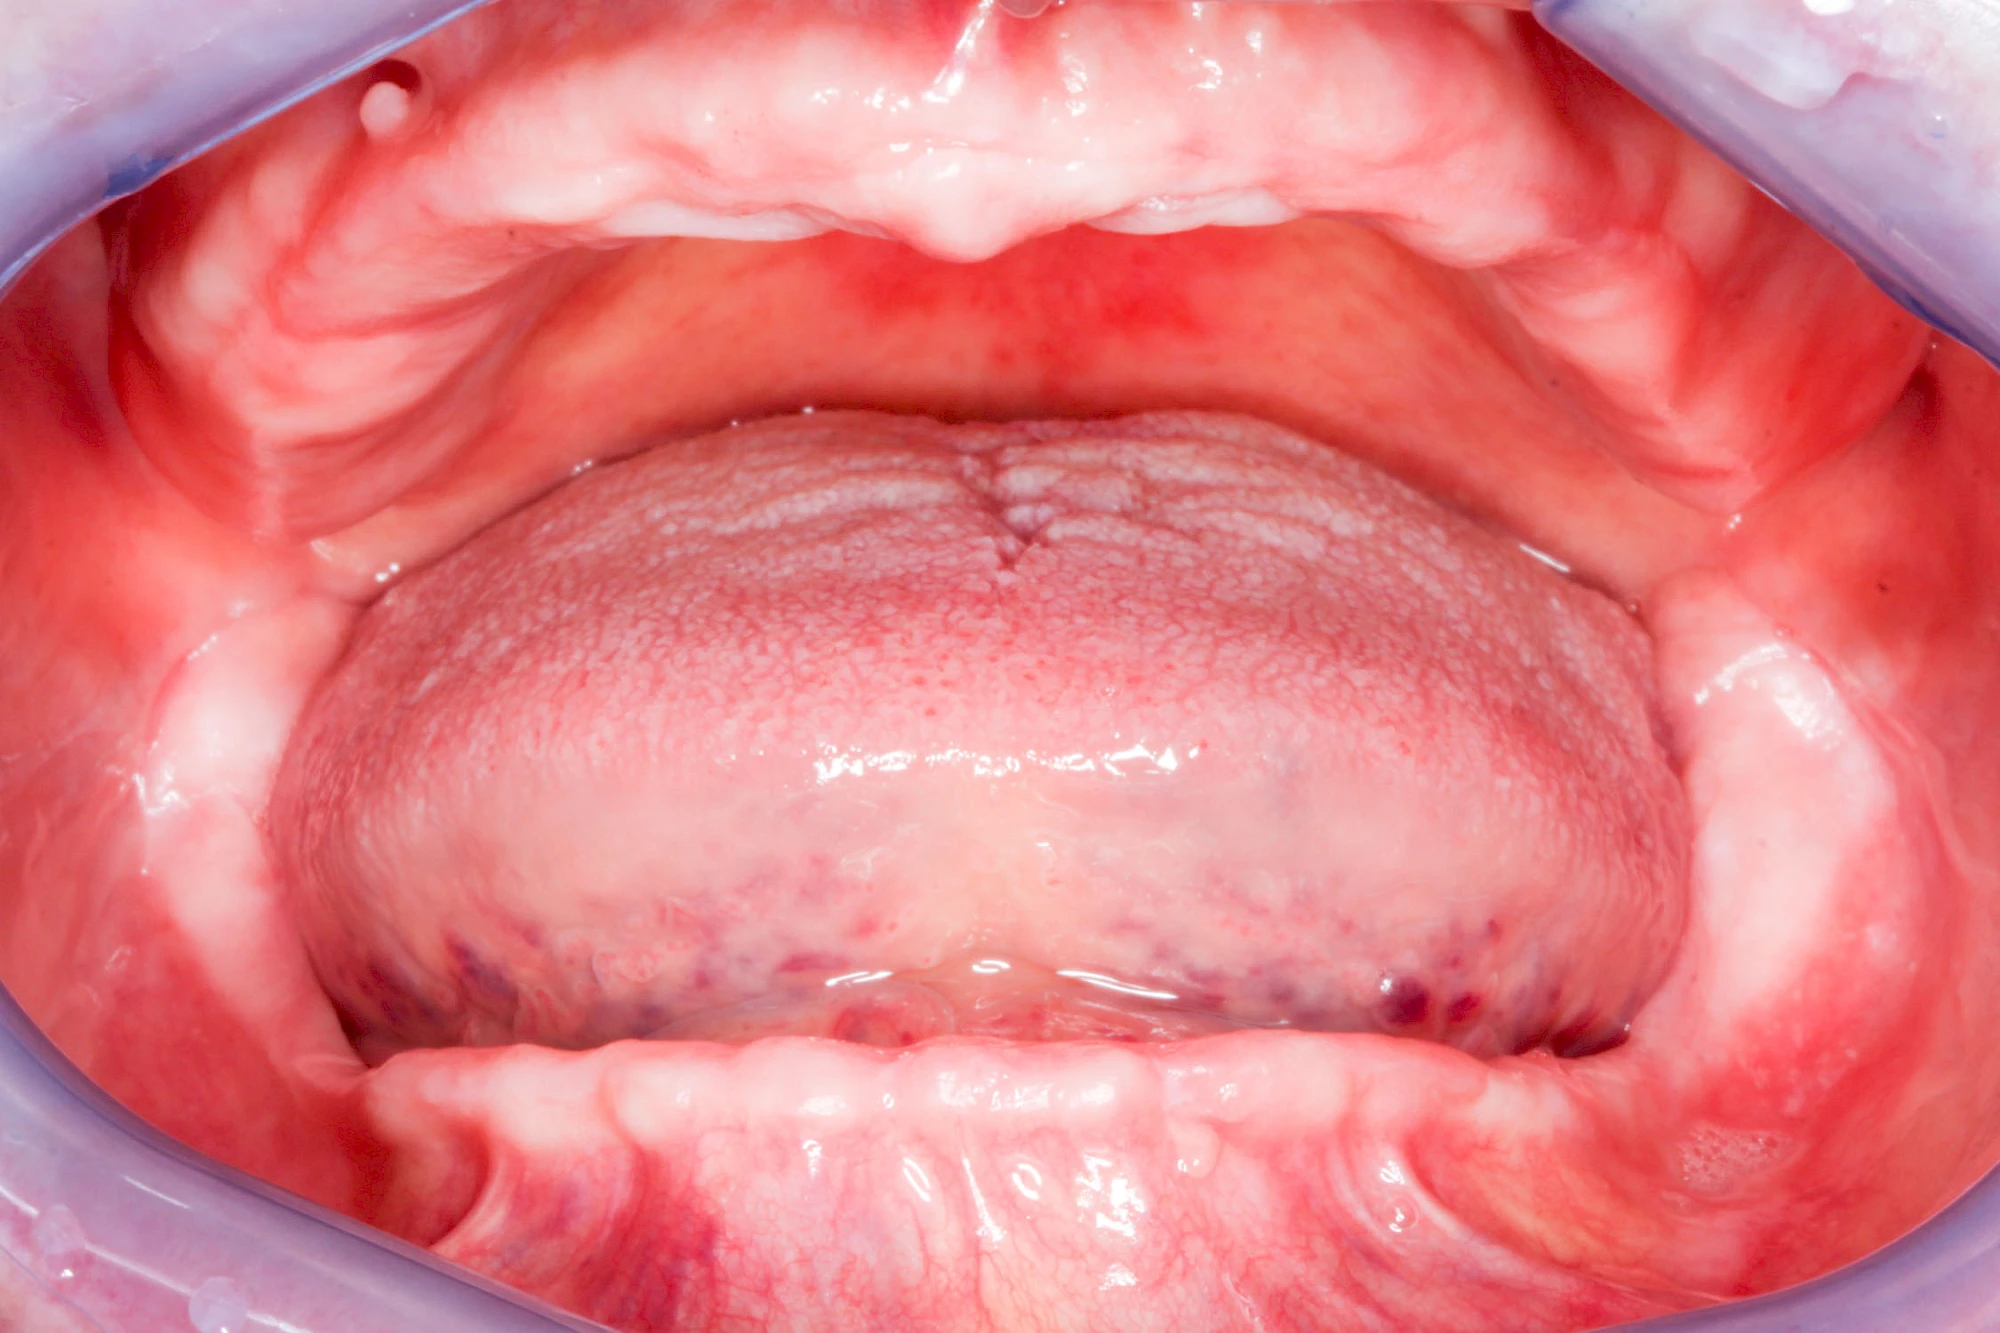

In jedem Fall sagen die Betroffenen, dass es sich ein paar Minuten komisch anfühlt, wenn sie die Zahnprothesen über Nacht aus dem Mund nehmen und dann morgens wieder einsetzen. Das ist normal und liegt daran, dass die Schleimhäute sich wieder regenerieren. Das ist gut für die Schleimhäute und Knochen im Bereich der Kiefer. Wir gehen ja auch nicht mit Schuhen ins Bett!

In seltenen Fällen schwindet nur der Knochen, aber nicht die bedeckenden Schleimhäute. In diesen Fällen spricht man von einem sogenannten "Schlotterkamm".